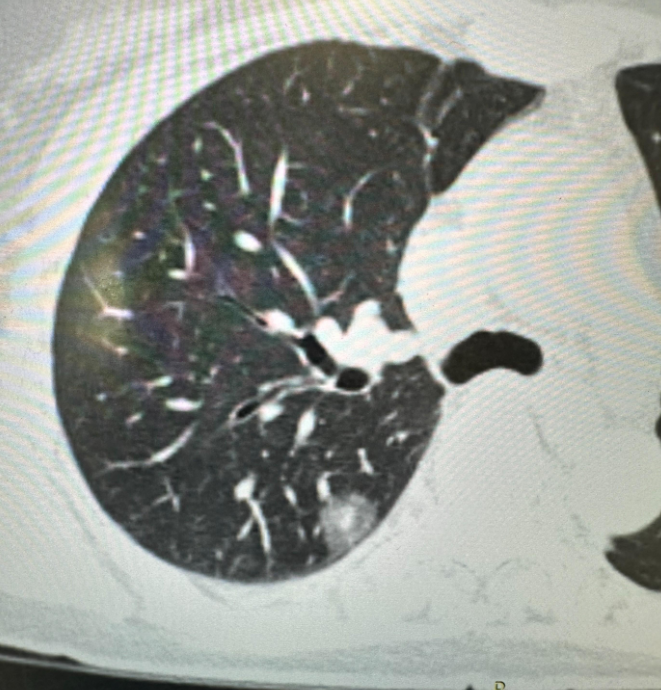

病理示:上叶原位癌,中叶浸润性腺癌,腺泡与贴壁各占50%.

图片尺寸1080x1439